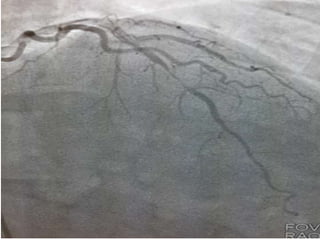

CASO CLINICO #3 MASCULINO 65 AÑOS DE EDAD DIABETES TIPO 2 DESDE HACE 15 AÑOS POBRE CONTROL METABOLICO DISLIPIDEMIA. OBESIDAD GRADO II. CUADRO CLINICO: ANGINA DE PECHO ATIPICA. CHEQUEO DE RUTINA. ECG DE REPOSO NORMAL. PRUEBA DE ESFUERZO POSITIVA Y PRECOZ PARA ISQUEMIA. TA 120/ 68 mm Hg. FC 67/min Fr 13/ min Glucosa en Ayunas 215 mg /dL. Colesterol total 260 mg/dL, LDL 135 mg d/L Creatinina 1.2 mg/dL EXAMEN FISICO ANODINO